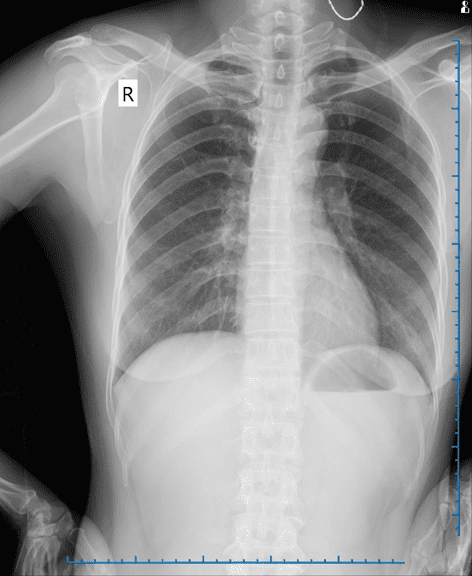

Phim chụp X-Quang của bệnh nhân

Qua các bước khám lâm sàng và cận lâm sàng chuyên sâu, các bác sĩ xác định vùng cổ bệnh nhân có một khối u kích thước 3x3 cm. Khối u có mật độ mềm, di động tốt, vùng da xung quanh không có dấu hiệu viêm nhiễm.